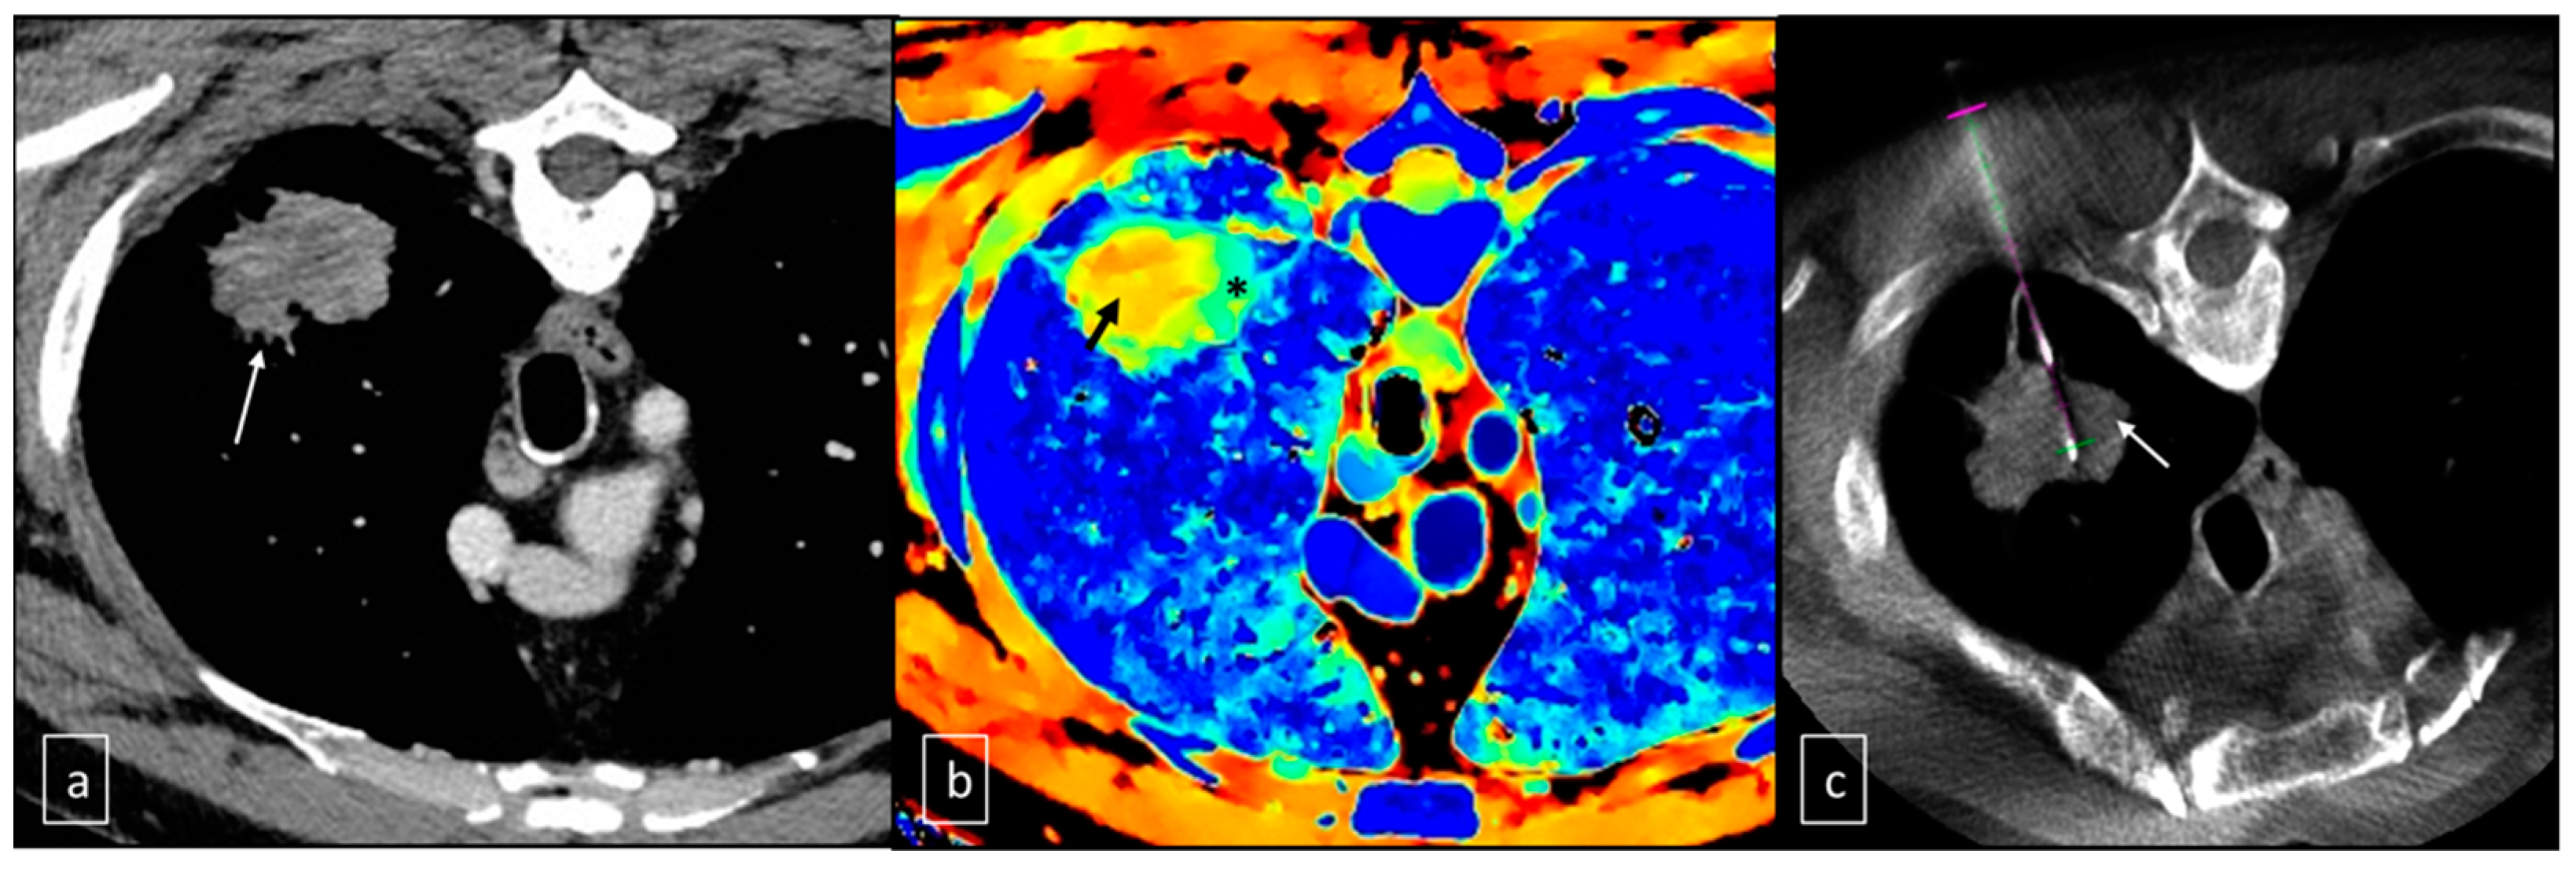

3. Results

- Curti, M.; Fontana, F.; Piacentino, F.; Ossola, C.; Coppola, A.; Carcano, G.; Venturini, M. Dual-layer spectral CT fusion imaging for lung biopsies: More accurate targets, diagnostic samplings, and biomarker information? Eur. Radiol. Exp. 2022, 6, 34. [Google Scholar] [CrossRef] [PubMed]